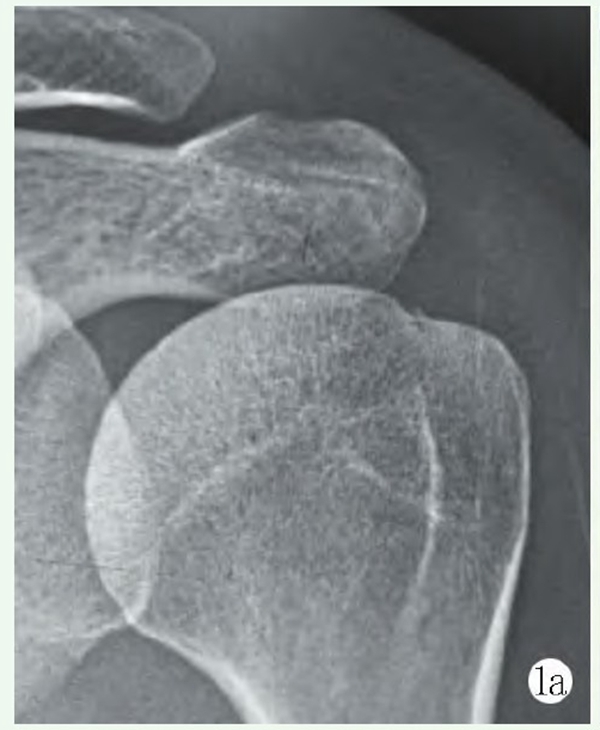

影像学检查X线片示肩峰外缘增生,肱骨头上移,肩峰-肱骨距离短缩,肱骨后方Hill-Sachs损伤。MRI示:右侧前下盂唇损伤,右侧肱骨后方Hill-Sachs损伤。右冈上肌全层撕裂并回缩,轻度脂肪浸润(图3a~3c)。

图3a: 术前MRI显示右侧前下盂唇损伤;3b: 术前MRI显示右侧肱骨后方Hill-Sachs损伤;3c: 术前MRI显示右冈上肌全层撕裂并回缩,轻度脂肪浸润